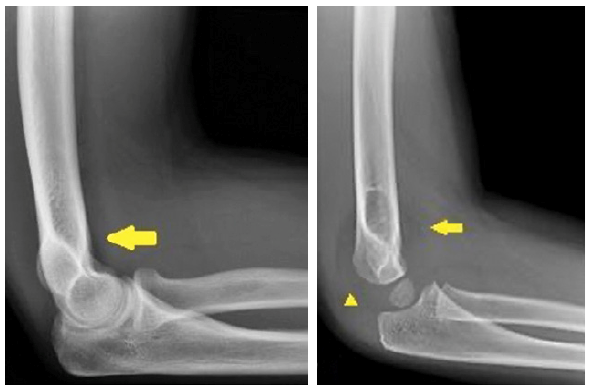

An AP film should be obtained with the elbow in full extension and the forearm supinated (Fig 1). For the true lateral projection, the elbow should be flexed 90 degrees with the forearm supinated. The routine use of comparative views is not recommended, as it comes at a considerable cost of radiation exposure to the child;1 several studies have shown that the routine use of comparative views does not alter patient management.2,3

The elbow fat pads are situated external to the joint capsule. On a true lateral radiograph, the normal anterior fat pad is seen as a radiolucent line parallel to the anterior humeral cortex; and the posterior fat pad is invisible.

Distention of a structurally intact joint causes displacement of the fat pads - the posterior fat pad moves posteriorly and superiorly and becomes visible; the anterior fat pad becomes more sail-like.4 (Fig 2)

On the lateral x-ray of the elbow, a joint effusion can be inferred when there is displacement of the anterior fat-pad or presence of the posterior fat pad. An elbow joint effusion without a visible fracture seen on radiographs can suggest an occult fracture and should prompt further evaluation.

A study by Major et al.5 showed that a joint effusion without visible fracture seen on conventional radiographs is often associated with an occult fracture and bone marrow edema on MRI. The study found that 57% of imaging where the only finding was joint effusion had a fracture and 100% had bone marrow edema on MRI. In cases where an occult fracture is suspected, follow-up radiographs in 7-10 days can be obtained to evaluate for the presence or absence of sclerosis or periosteal new bone formation as indicators of healing. For suspected occult fractures, standard of care remains posterior elbow splinting with follow-up radiographs at 7-10 days.